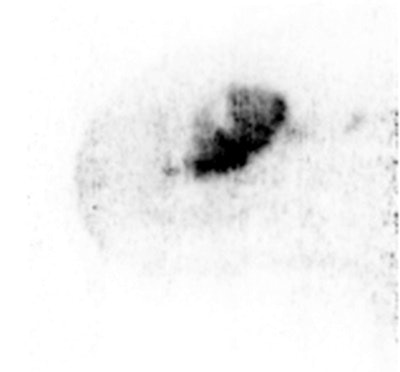

Sagittal Mammi-PET image shows one FDG-avid lesion. Inside the lesion, regions can be identified with different FDG uptake. This heterogeneity may be correlated in the future with different characteristics of the same tumor, when biopsies of the various regions are compared.Teixeira and her and colleagues plan to continue their research by trying to identify, at least visually, heterogeneous uptake within primary cancer lesions with the development of a Mammi-PET device with an integrated FDG-guided biopsy system.